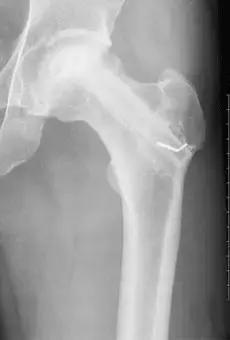

股骨头坏死Ⅰ期。治疗时间约半年以上的时间,早期及时诊断并按医嘱治疗,一个疗程可以有明显好转,股骨头不仅形态完好而且X线片显示死骨区吸收,骨密度恢复。疼痛缓解、股骨头基本可保住。

股骨头坏死Ⅱ期。治疗时间约十个月以上,早期及时诊断并按医嘱可使坏死囊变区的新骨再生。X片显示有新生骨小梁通过。

股骨头坏死Ⅲ期。治疗时间约一年以上,三个疗程后死骨已全部吸收,大部分骨小梁基本上通过,疗程结束后股骨头死骨全部吸收完,股骨头轮廓及部分的骨质变化清晰。

股骨头坏死Ⅳ期。治疗时间约一年半以上,坏死骨完全吸收,也能够将死骨区吸收。通过大量的新生骨小梁的增加、填植,股骨头能够重愈,但股骨头形态不饱满、圆滑。